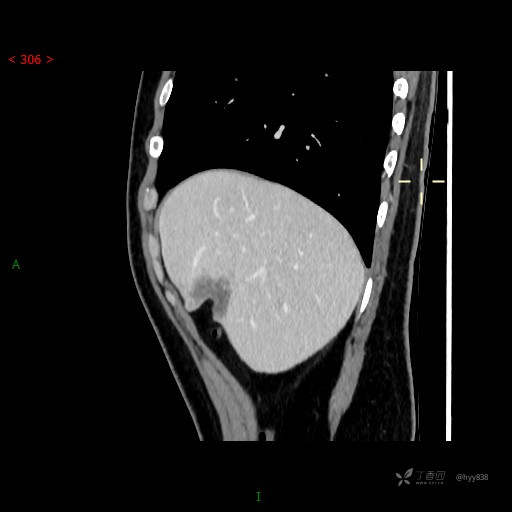

年轻男性,肝脏孤立结节、邻近包膜如此内陷,不知“坑”为何物---(结果公布)

简要病史: 患者1月余出现腰背部疼痛,以夜间疼痛为甚,伴双下肢胀痛,无腹胀、腹痛,无咳嗽、咳痰,无头晕、头痛等症状,门诊超声提示肝结节状占位

临床诊断:肝占位

肝脏CT平扫